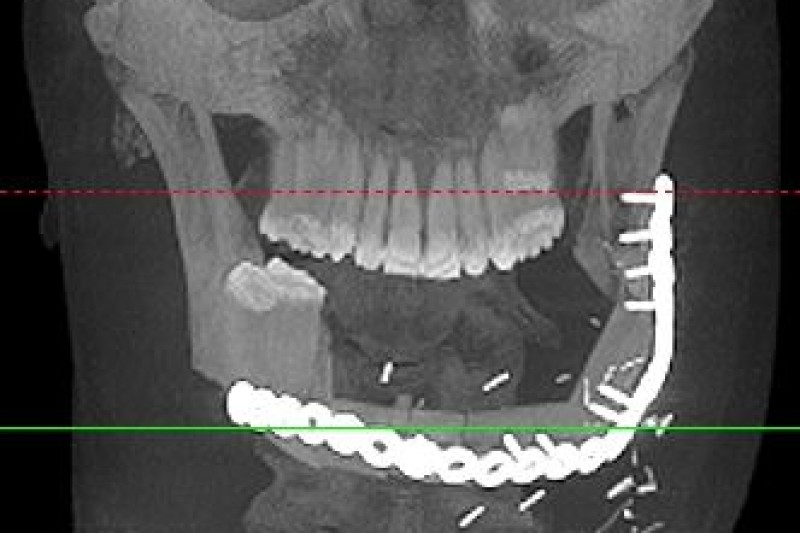

In 2015 my brother Vince was diagnosed with a very rare tumor in his jaw called Ameloblastoma. The diagnosis came after he had been misdiagnosed and treated incorrectly for almost 2 years. Vince was referred to the great doctors at HUP who told him he would need the tumor and 25% of his jaw removed. His insurance denied the surgery and all related medical claims over many months.Fighting with the insurance company led to a delay in care which allowed the tumor to grow and ultimatley caused a surgury requiring the removal of 85% of his jaw, all but two of his bottom teeth and a complete reconstuction of a new jaw in March 2016. This long battle has lead to medical bills adding up to tens of thousands of dollars. He will need 2 more procedures and pay out of pocket for his replacement teeth.Vince needs teeth and help with the bills his insurance company denied. Vince is a great brother, father, son and friend. If you know him, you know he is always there for the people who need him. We have started a non profit called Vincent DiCostanzo's Big Dumb Face Foundation so all donations are tax deductible!! No donation is too small. Thank you!!!